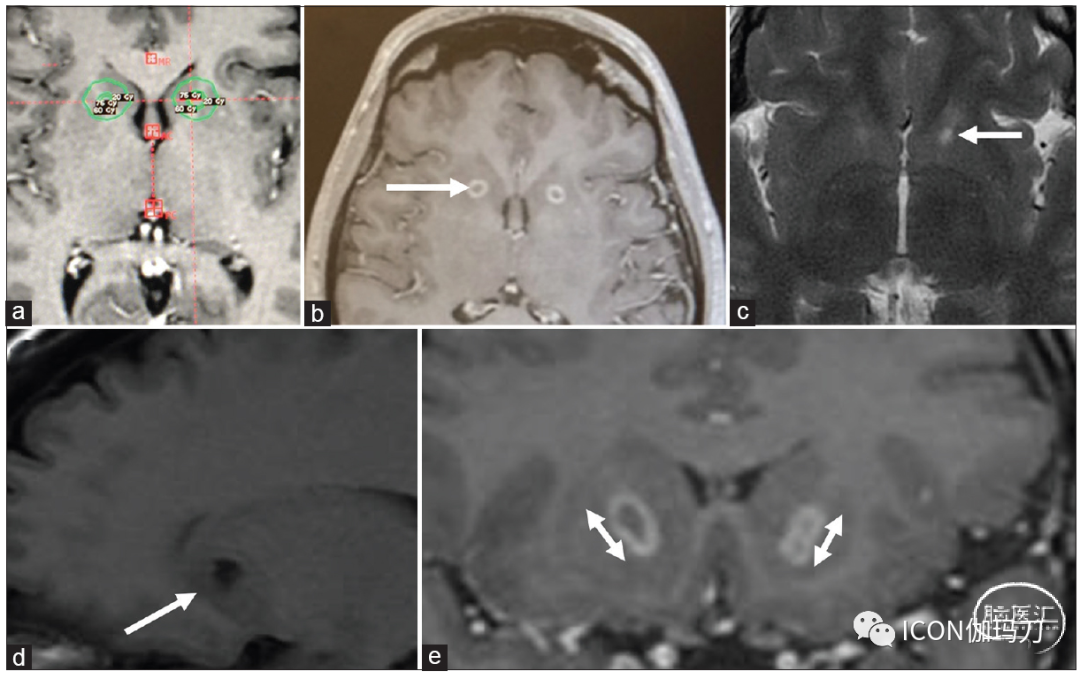

在获得必要的影像学后,确定Genu(膝部)和ALIC(内囊前肢)。以ALIC壳核中点为靶心,两侧各设2个4 mm等中心点,形成近似椭圆形的剂量分布区域。处方等剂量靶点的覆盖范围,特别是在ALIC的基底(腹侧)部分,根据传导束造影进一步调整。每侧最大剂量为120 Gy,内囊前肢包括在70%等剂量线区内[图2]。

图2:(a) T1 MRI显示强迫症双侧内囊前肢毁损术轴位计划。(b)水平箭头显示130Gy治疗6个月后强化病灶。(c) T2 MRI显示壳核中点病灶的精确位置。(d) T1 MRI显示慢性病变。(e) T1 MRI对比增强显示内囊前肢最腹侧两个部位的病灶大小。病变达到130 Gy,每边两个等中心点,4毫米准直器。